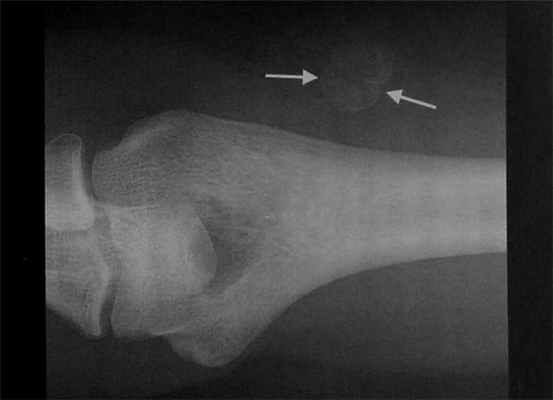

Мужчина 29 лет с болевым синдромом в верхних отделах правого плеча и наличием затруднений при разгибании в плечевом суставе в течение 2 мес. Отсутствие травмы в анамнезе. Рентгенография локтевого сустава. Четко ограниченный, с гладким краем округлый участок окостенения в мягких тканях латеральнее дистального отдела плечевой кости. Оссифицирующий миозит, подтвержденный при рентгенологическом исследовании.

Что покажут снимки КТ костей конечностей при оссифицирующем миозите

- Зональная структура (кальцинированная периферическая зона с некальцинированным центром) определяется лучше, чем при рентгенологическом исследовании

- Лучше визуализируется расстояние от кортикального слоя расположенной рядом кости.